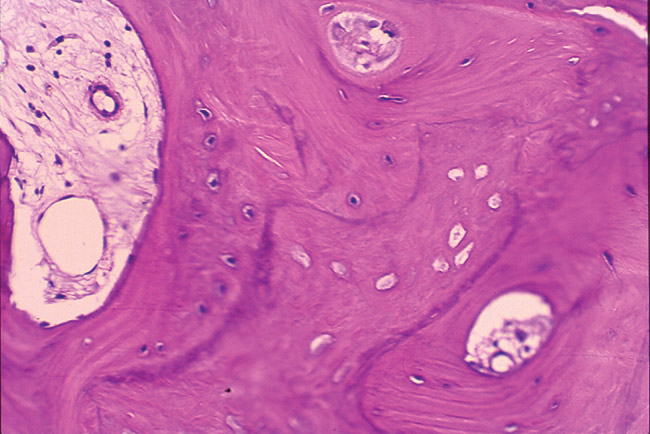

The histology report included the presence of viable bone consisting of anastomosing trabeculae surrounding Haversian systems. The Haversian systems contain connective tissue with variably sized, endothelial-lined vascular spaces. The bone formation is primarily lamellar. Osteocytes are present within the lacunae. Abundant fibrous connective tissue is present at the periphery of this soft-tissue specimen, and woven bone is observed in the dense connective tissue. Fragments of calcified debris are admixed with the periphery of this decalcified specimen. The viable bone exhibits prominent resting and reversal lines. A diagnosis of viable sclerotic bone was made.

Figure 2d  The histology report included the presence of viable bone consisting of anastomosing trabeculae surrounding Haversian systems

Figure 2d

Figure 2e  The bone formation is primarily lamellar. Osteocytes were present within the lacunae. Woven bone was observed in the dense connective tissue. Fragments of calcified debris are admixed with the periphery of this decalcified specimen. The viable bone exhibits prominent resting and reversal lines. A diagnosis of viable sclerotic bone was made.

Figure 2e